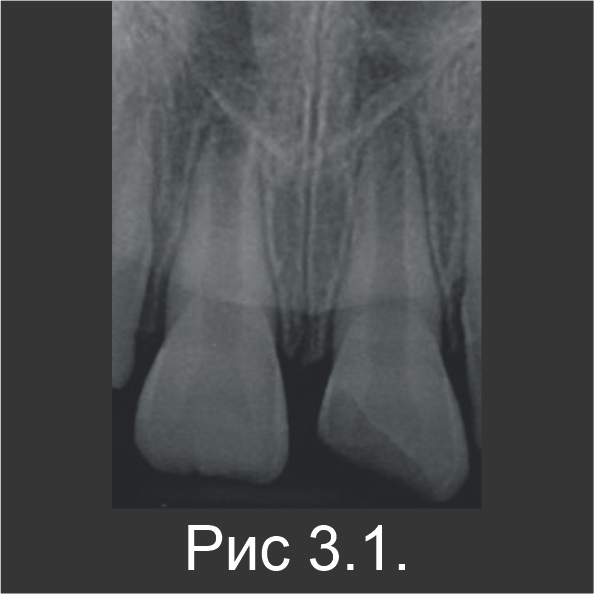

У 7-летнего мальчика произошел осложненный перелом коронки зуба 21. Это произошло во время занятий спортом (рис. 3.1). В зубе 21 наблюдалась чувствительность к перкуссии, а пульпа была открытой. Пациенту ввели местный анестетик, а участок перелома очистили промыванием физиологическим раствором. Непосредственно на открытую пульпу нанесли Biodentine™, который также оставили в качестве временной пломбы (рис. 3.2).